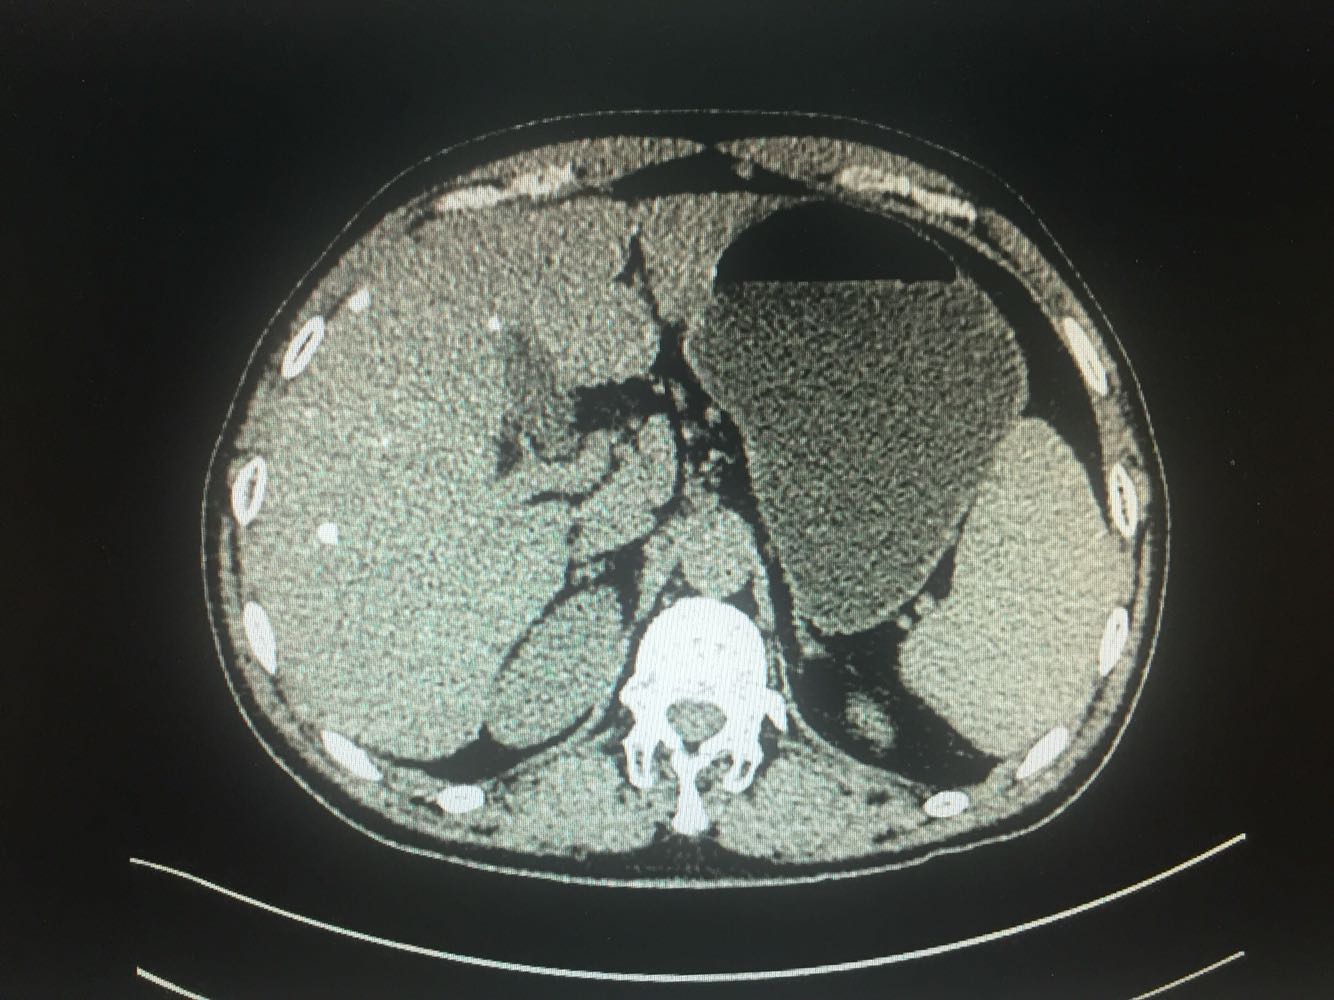

查体:体温,36摄氏度,脉搏:60次/分,呼吸,19次/分、血压,115/70mmhg,发育正常,营养欠佳,皮肤黏膜,色泽正常,双侧眼睑正常,双侧巩膜无黄染,口唇红润,双肺呼吸音清晰,心率60次/分,心律齐,心音有力,无病理性杂音。右上腹部饱满,中上腹压痛明显,肝脏肋下2cm触及,质地硬,触痛阳性,脾肋下2cm触及,移动性浊音阴性,肠音正常,双下肢无水肿 化验:血常规:白细胞计数2.9*10~9/L,中性粒细胞1.4*10~9L,红细胞计数4.03*10^12L,血小板计数76*10^9/L;生化全套。血糖4.67mol/L,总蛋白81.0g/L,白蛋白40.9g/1L,丙氯酸氨基转移酶256U/L,天门冬氨酸氨基转移酶182U,总胆红素22.0umol/L,胆碱酯酶4479U/L,Y-谷氨酰基转移酶137U/L;传染病9项:乙型肝炎病表面抗原阳性/6380,乙型肝炎病毒e抗体阳性/0.004,乙型肝炎病毒核心抗体阳性/0.008 肿瘤标志物:甲胎蛋白415.50ng/ml,乙型肝炎病毒DNA测定2.06E+07IU/ml CT:1.考虑肝右叶巨块型肝癌伴肝内多发转移,2.肝门部及腹膜后、心隔角旁小淋巴结。3.肝小囊肿。4.肝左叶増大。5.肝脏钙化灶。6.副牌。7.双肾微小囊肿

乙肝肝硬化,原发性肝癌,保肝抗病毒治疗,及TACE

出院一月后复查,行增强CT扫描,肿瘤明显缩小,肝功能正常,乙肝病毒复制转阴,建议继续口服恩替卡韦抗病毒治疗